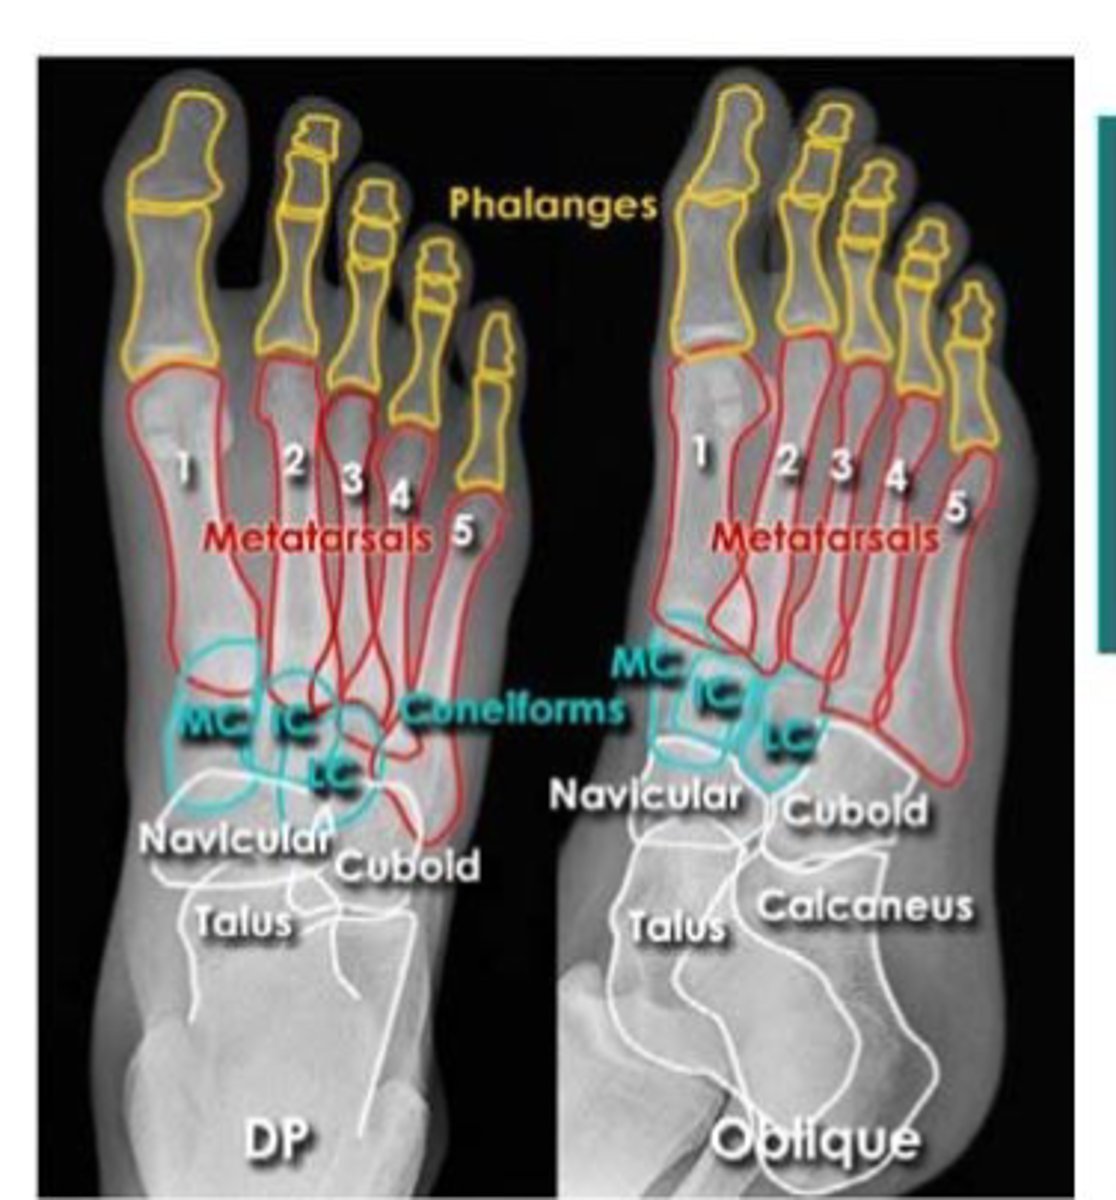

foot

knowt flashcard image